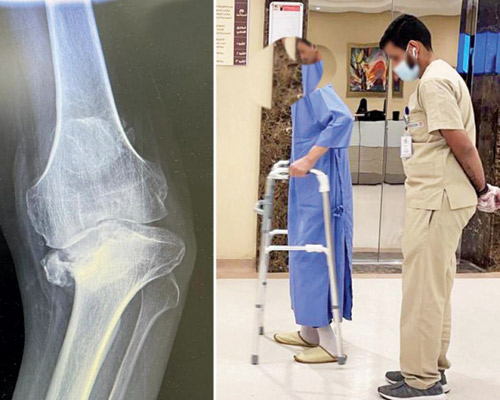

وأوضح أ.د.الجاسر أن المريض كان قد تعرض لحادث مروري قبل «10» سنوات أدى إلى إصابته بكسر مضاعف في الساق اليمنى، وكسر آخر غير متحرك في الركبة اليسرى، وهو ما دفعه إلى الاعتماد على الساق اليسرى، التي أظهرت الأشعة إصابتها بخشونة من الدرجة العالية وتقوس حاد، استدعى تدخلاً جراحياً مدعوماً بأحدث الأجهزة والتقنيات الطبية، حيث تم فيها استبدال مفصل الركبة اليسرى، وزراعة دعامة في الفخذ وأخرى بالساق، وثالثة جانبية للمحافظة على استقامة الركبة واستقرارها.

وأكد أ.د.الجاسر أن العملية التي استمرت نحو «3» ساعات، حققت ولله الحمد نجاحاً متكاملاً، وقد تم تحويل المريض بعدها إلى غرفة تنويم، أمضى فيها «4» أيام قيد الملاحظة والعلاج الطبيعي، وشهدت حالته تحسناً مطرداً أكدته التحاليل المختبرية وصور الأشعة التي أجراها بعد العملية لاستكشاف وضع المفصل الجديد، وبفضل الله بدأ المريض بالمشي والحركة مع أخصائي العلاج الطبيعي.